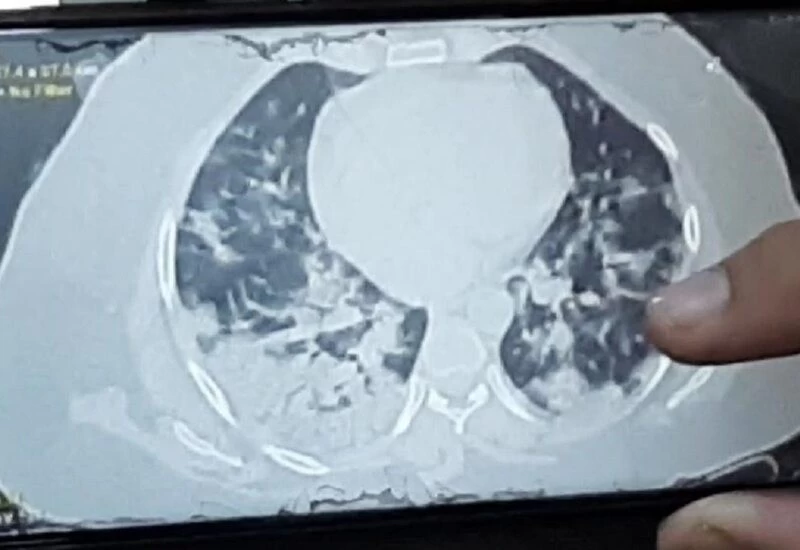

महिला 13 तारीख को खड़ी भी नहीं हो पा रही थी, सांस लेने में दिक्कत हुई तो चेक करने के बाद पता चला कि ऑक्सीजन लेवल 94 था। 13 तारीख को सिटी स्कैन करवाया तो उसके दोनों लंग्स मैं 80 परसेंट तक इंफेक्शन लग चुका था।

यह देख कर कोटा के स्वास रोग विशेषज्ञ डॉक्टर के के डंग भी चकित रह गए कि मात्र 24 घंटे में लंग्स इतने खराब हो सकते हैं। उन्होंने इंदौर के विशेषज्ञ डॉक्टर से परामर्श किया तो उन्होंने बताया कि यह नया स्ट्रेन है जिस वजह से ऐसा हुआ है।